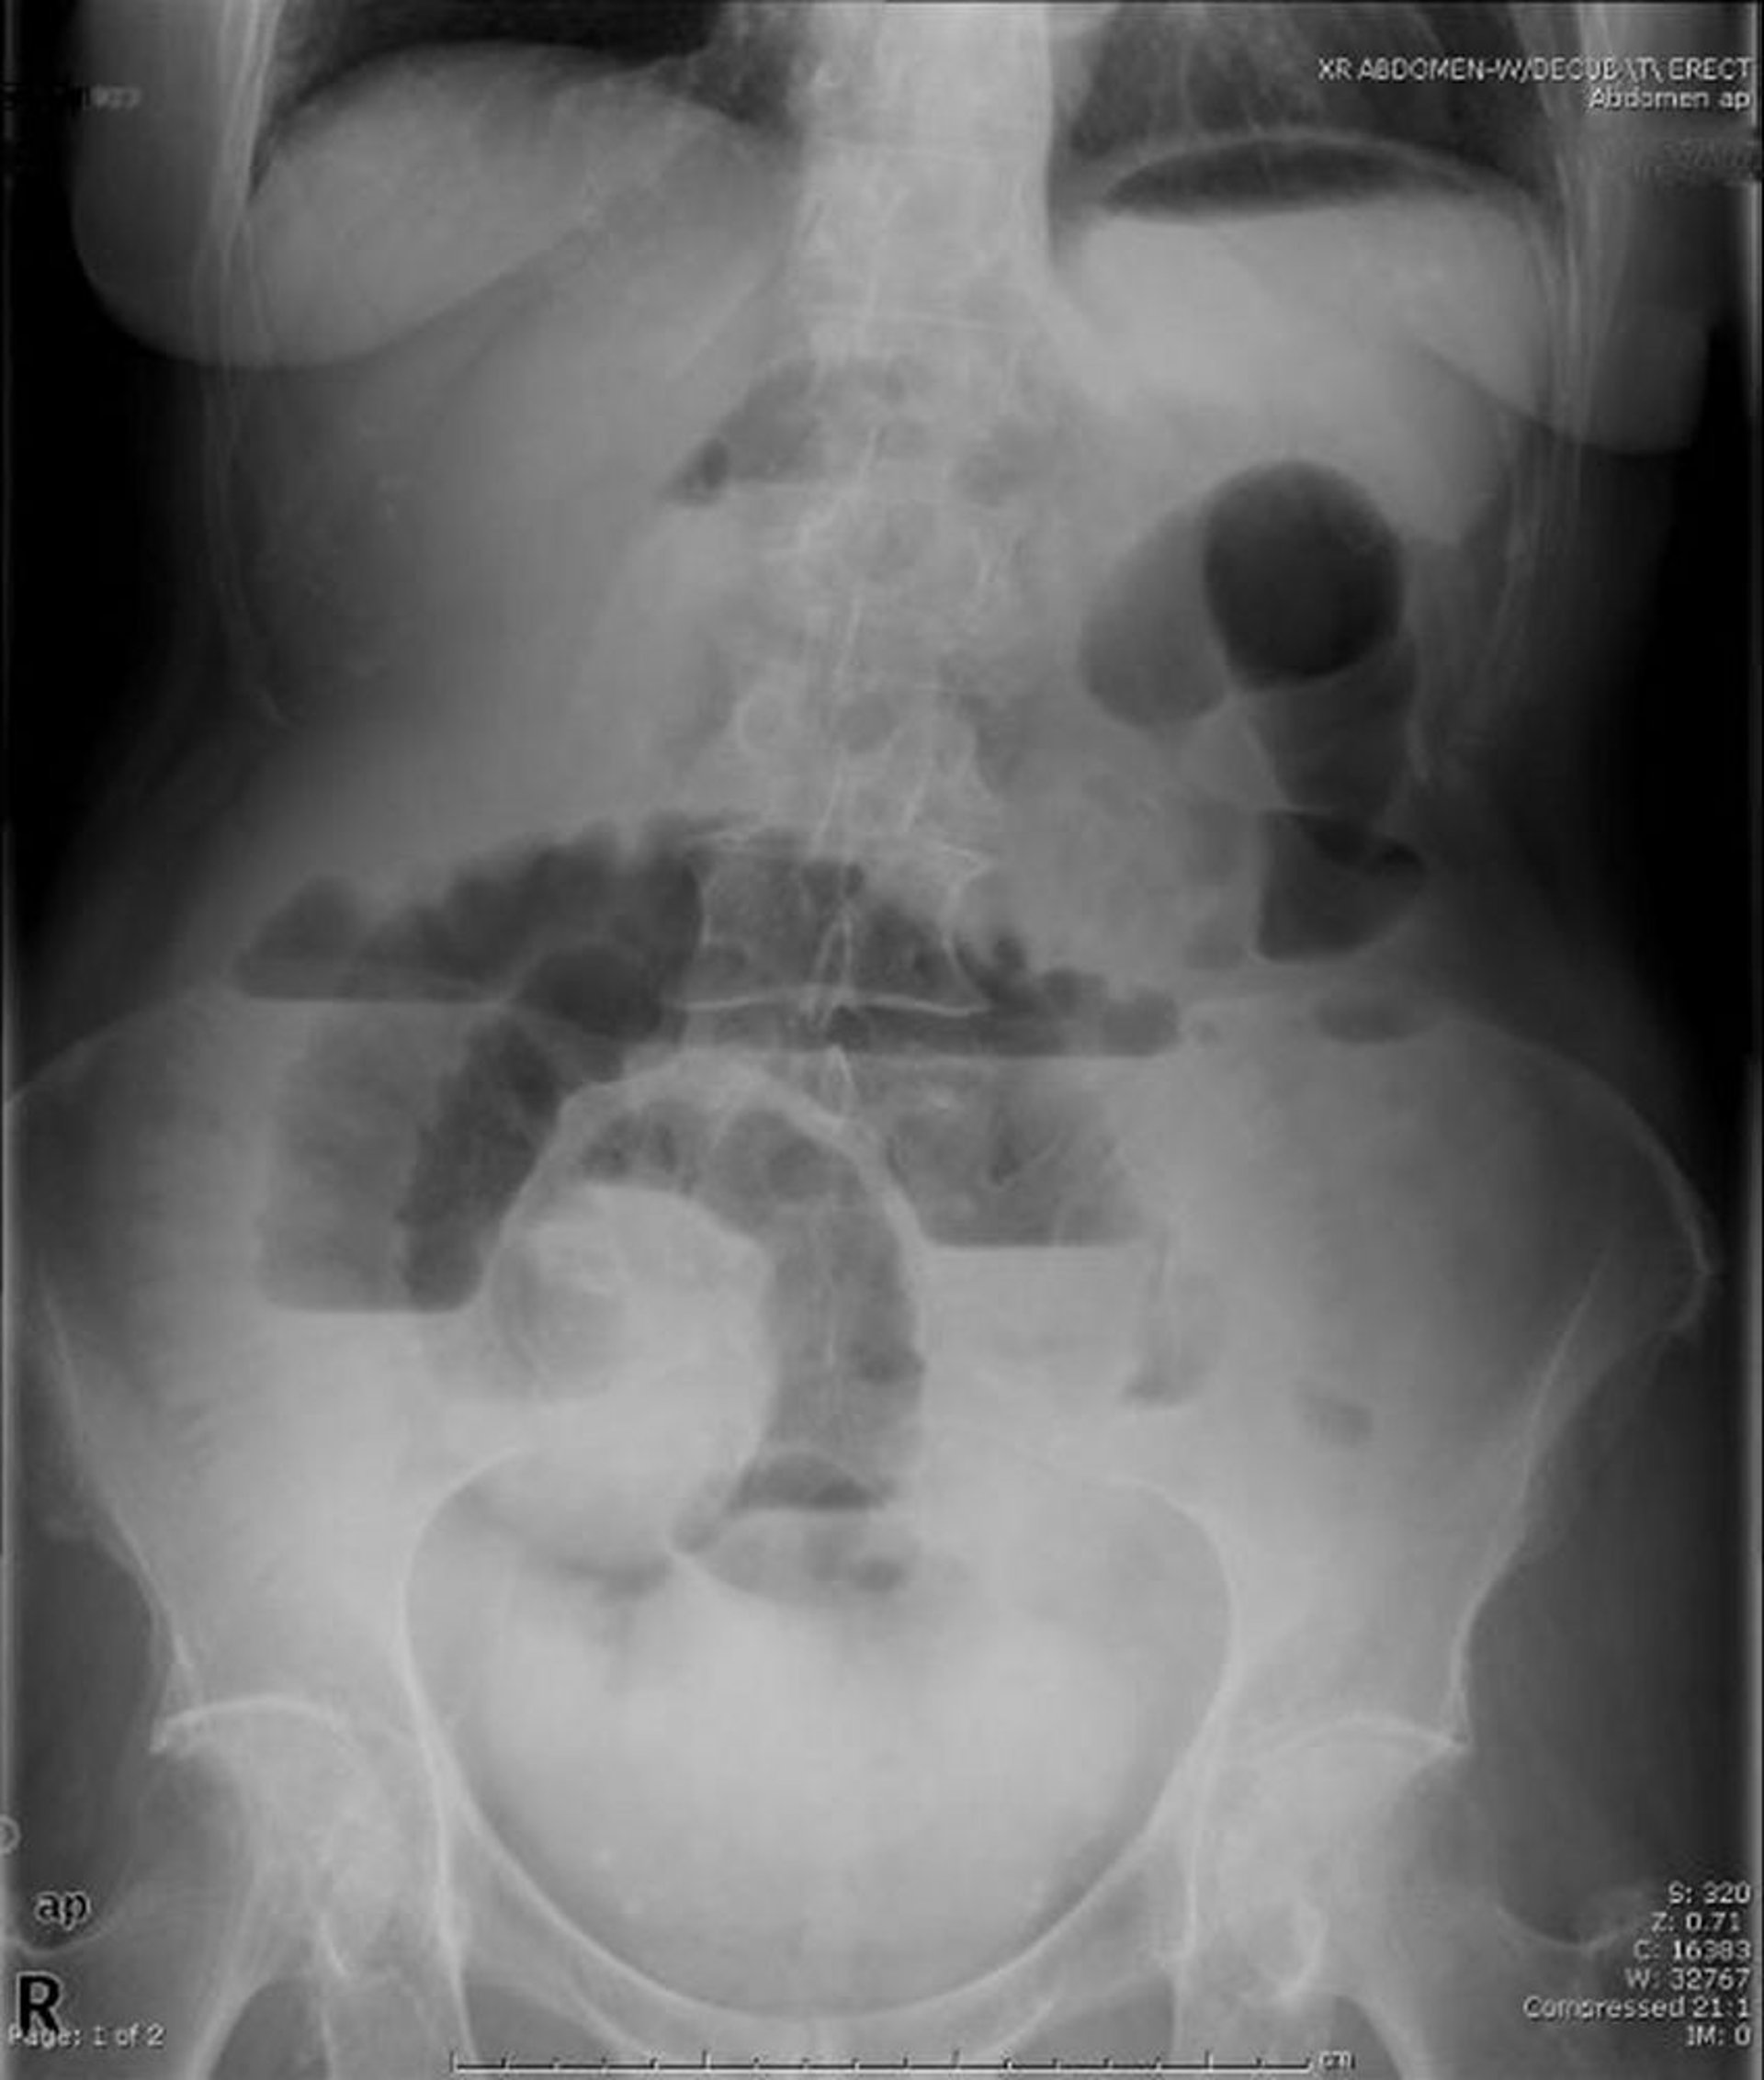

Obstrução do intestino delgado (radiografia vertical)

Essa radiografia abdominal na posição vertical mostra obstrução do intestino delgado. Observe os múltiplos níveis hidroaéreos.

Image provided by Parswa Ansari, MD.